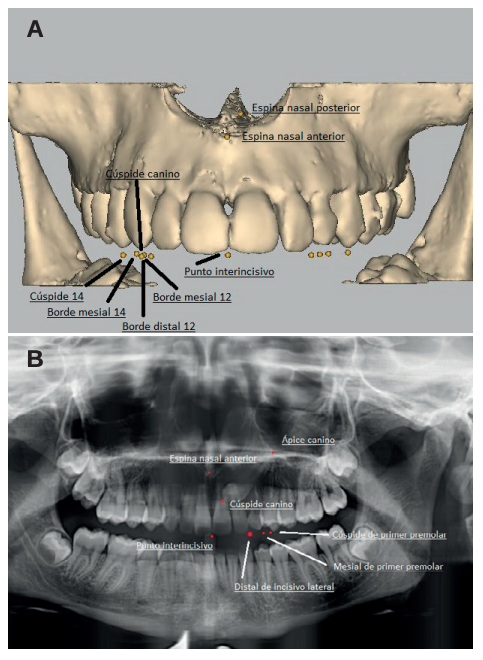

Methods: An orthodontic study of the maxilla using orthopantomography with cone beam computed tomography (CBCT) at the Madrid European University Clinic was performed on 27 patients selected with 36 maxillary impacted canines. Three reference lines were drawn based on the distance from the cusp of the canine to the occlusal plane (L1), to the midline (L2) and to its ideal eruption site (L3), in both the orthopanthomography and the CBCT. As ideal reference values, we selected a control group of 36 erupted maxillary canines.